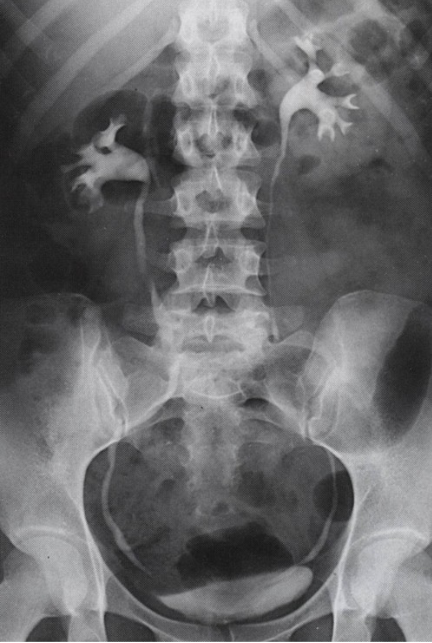

What contrast procedure was performed to produce this image?

IVU – Intravenous Urogram

1)procedure performed?

2)contrast media used?

3)How contrast media administered?

4)List contraindication for this type of contrast media:

1)IVU – Intravenous Urogram

2)Water-Soluble Iodinated

3)Injected intravenously (bc travels through the bloodstream → filtered by kidneys → passes through renal pelvis → ureters → bladder)

4)dont use if: Allergic; Poor kidney function / renal failure; Dehydration; Severe asthma or thyroid disorders